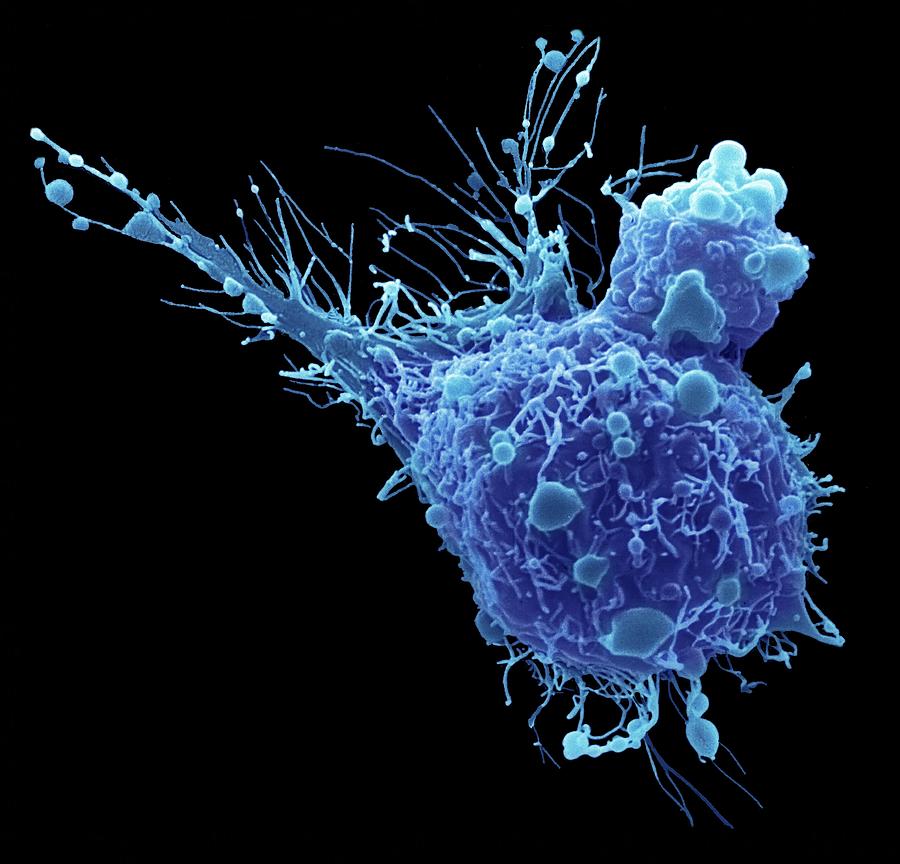

Bladder Cancer Photograph by Zephyr/science Photo Library – Pixels

Bladder Cancer Photograph by Zephyr/science Photo Library

Bladder Cancer Photograph by Zephyr/science Photo Library

Bladder Cancer Cell Photograph by Steve Gschmeissner/science Photo Library

Bladder Cancer Cell, Tem Photograph by Steve Gschmeissner